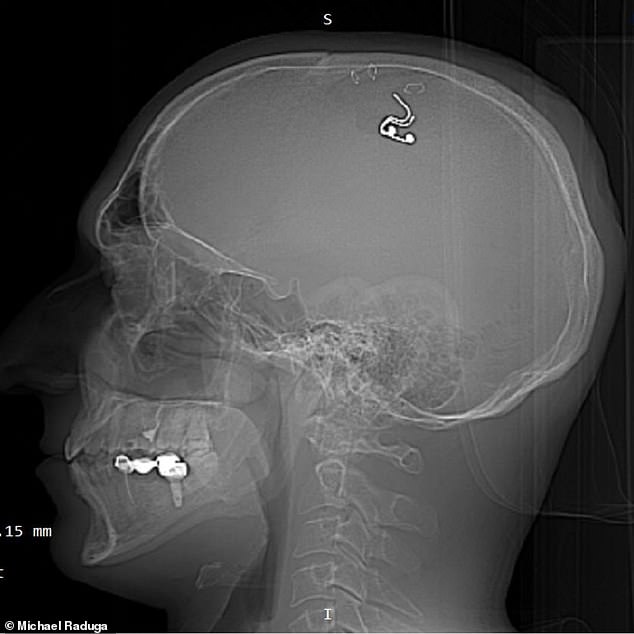

Now, with his new platinum and silicon implant, he claims to have taken this up a notch, using the power of electricity to trigger certain actions in dreams.

He inserted the chip into his brain after watching hours of neurosurgery YouTube videos and practicing on five sheep - he told no one of his plans.

While this was eventually removed in hospital after five weeks, Phase Today followers have already been asked whether they would be 'willing to get a brain implant for more efficient lucid dreaming'.